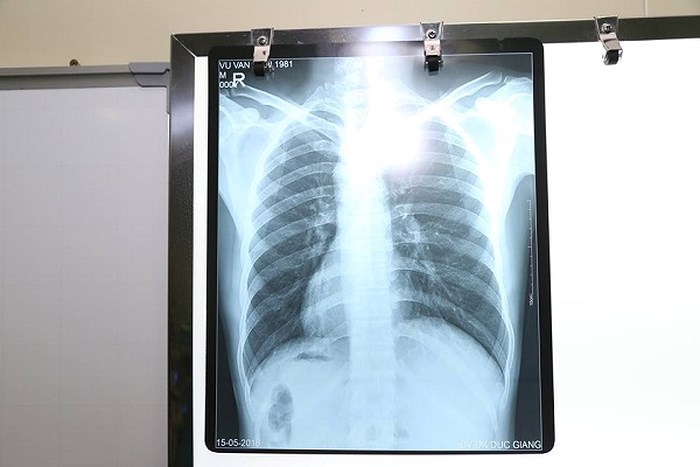

| Kết quả chụp Xquang cho thấy bệnh nhân có phủ tạng nằm đảo ngược hoàn toàn so với bình thường |

Sau khi thăm khám, xét nghiệm, siêu âm, chụp Xquang, các bác sĩ rất bất ngờ với hình ảnh trái tim cùng với các phủ tạng khác trong lồng ngực và bụng của bệnh nhân H. ở vị trí "soi gương" so với bình thường. Tức là, trái tim và dạ dày ở bên phải, còn gan và ruột thừa thì ở bên trái.